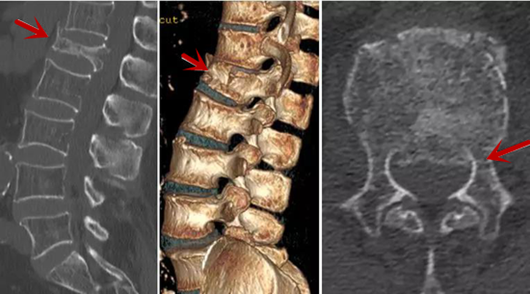

箭頭提示椎間盤突出

從左向右依次為CT矢狀位重建圖像、三維重建圖像、軸位掃描圖像,箭頭提示腰1椎體爆裂性骨折